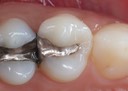

Joe Cha #3 amalgam removal